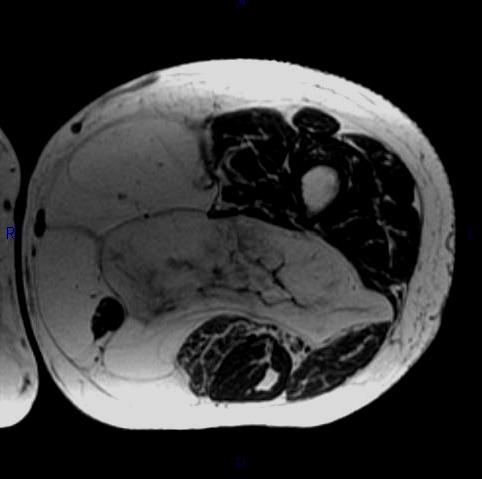

MRI (Fig. 1, 2, 3 and 4)

• Large encapsulated lipomatous mass. (Fig. 1, 2, 3 and 4)

• Greater than 75% adipose tissue (Hyperintense on T1-weighted) (Fig. 1)

• Nonadipose components; prominent thick septa and focal nodular regions usually less than 2 cm in size. (Fig. 3)

• Loss of signal on fat-saturated T1-weighted images.

• MRI does not appear homogeneous. (Fig. 4)

• High signal on T1 and low signal on T2 fat suppressed

• Fibrous stranding typical

Fig. 2-4 MRI: Coronal T2-weighted fat suppressed (Fig. 2) and Axial T2-weighted FS (Fig. 3) shows low intensity signal isointense with fat. Adypocitic lesion with fatty signal is located in the posterior and medial compartment of the thigh. Thickened septa and nodularity enhances on post contrast images. (Fig. 4)